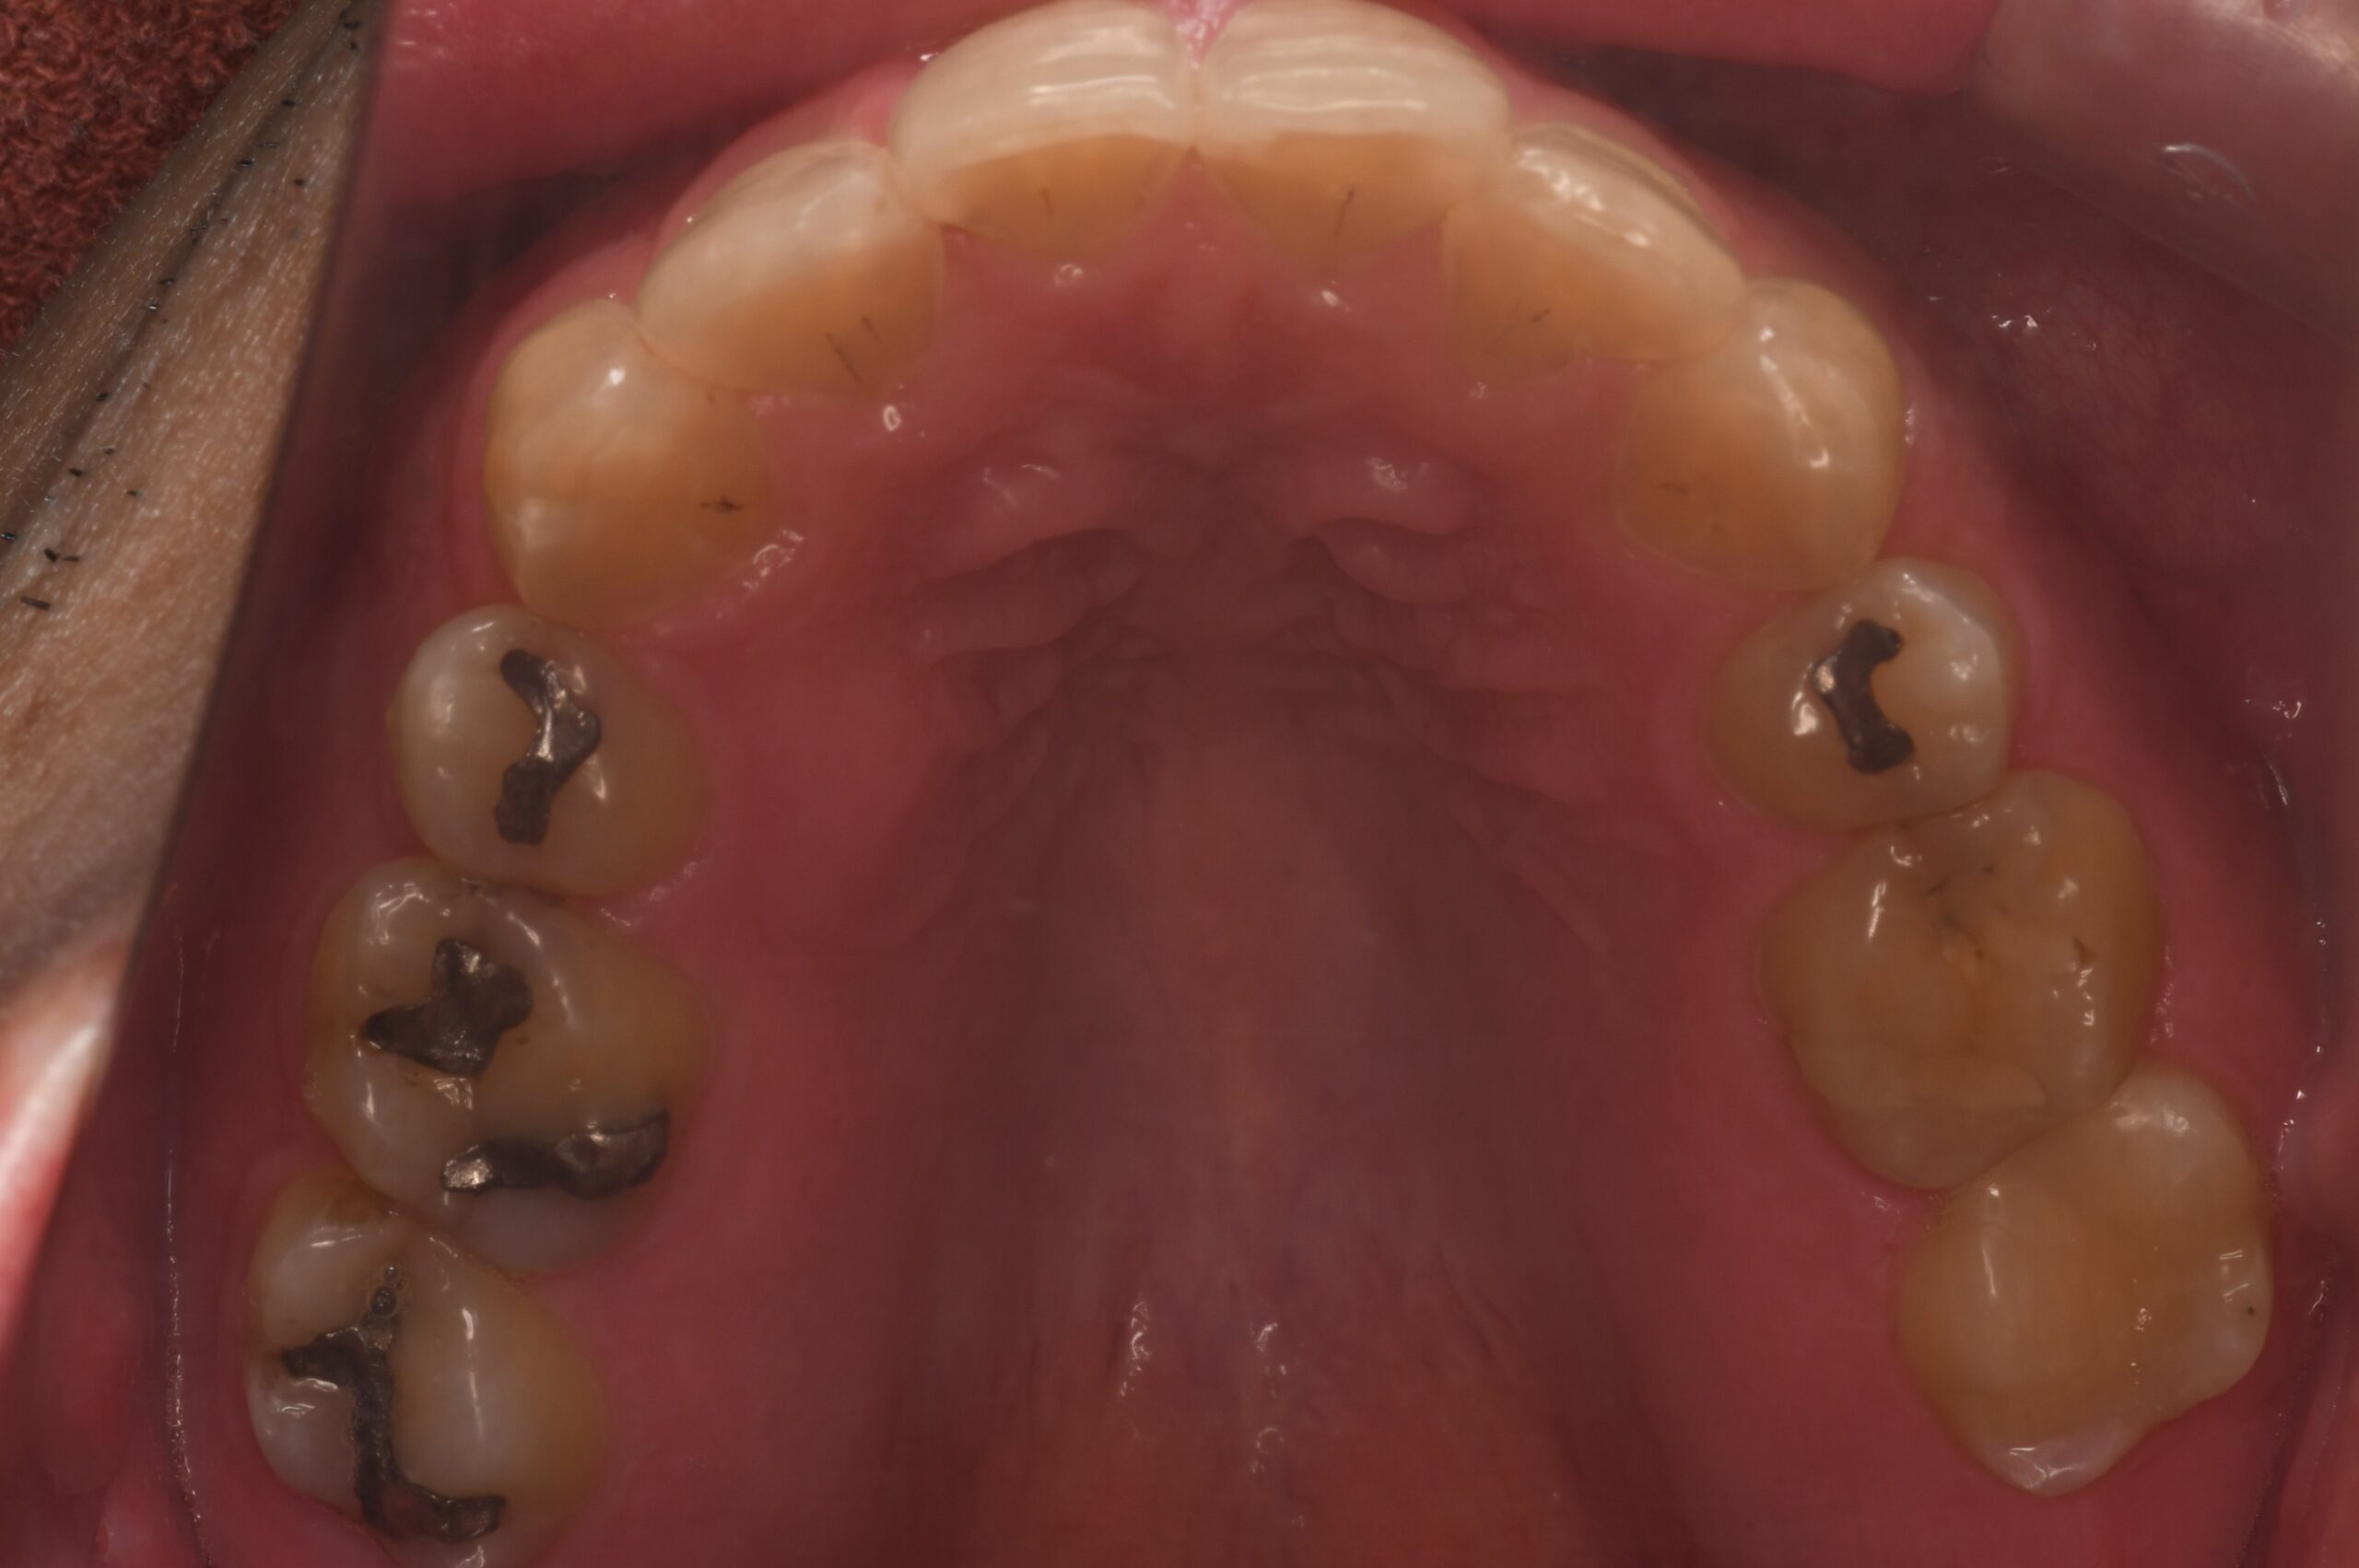

AFTER

| 年齢 | 45歳 |

|---|---|

| 主訴 | 矯正治療の後戻りを治したい |

| 症状 | 上下両側第一小臼歯抜歯による矯正既往を有する叢生症例 |

| 治療内容 | 上下両側第一小臼歯抜歯による矯正既往を有する叢生症例と診断し非抜歯(上下両側第一小臼歯抜歯済み)でマウスピース型(カスタムメイド)矯正(歯科)装置を用いて治療を行いました。 |

| 抜歯部位 | 非抜歯(上下両側第一小臼歯抜歯済み) |

| 治療期間 | 6か月 |

| 費用(税込) | 990,000円(税込)別途処置料 |

| 治療のリスク | 虫歯、歯周病の悪化、歯肉退縮、歯根吸収、顎関節症の悪化、後戻り |